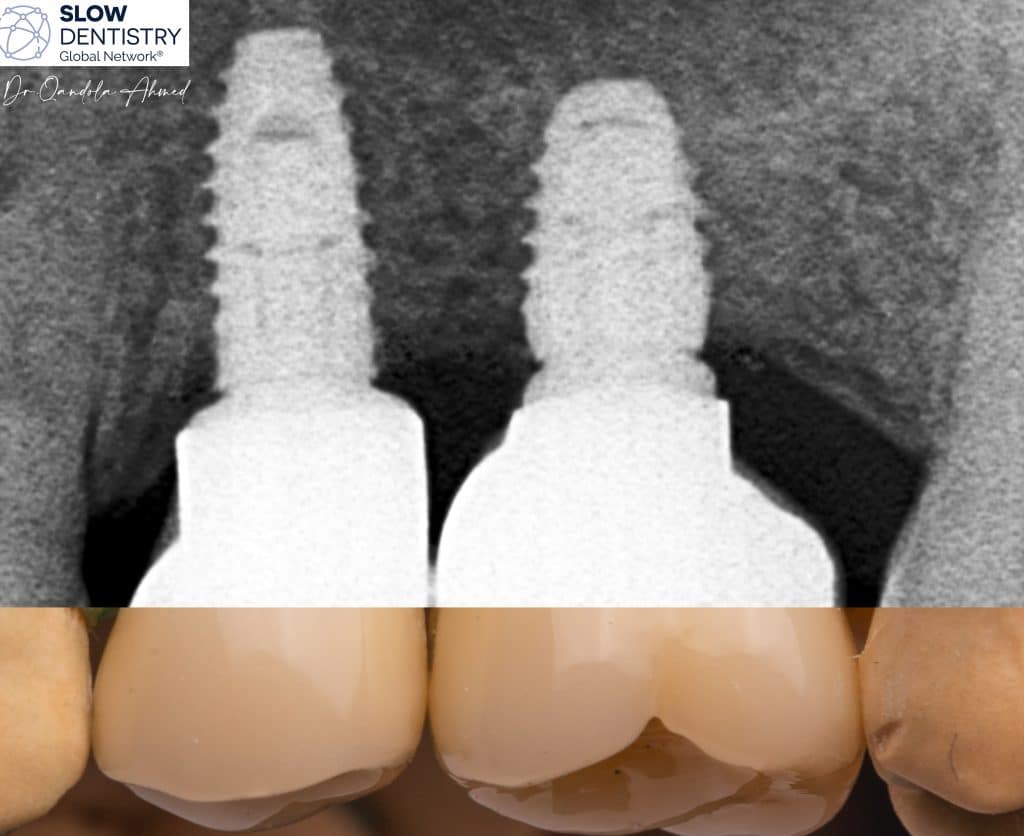

When considering the question of whether dental implants should be separated or splinted, it is essential to weigh the advantages and disadvantages of each approach.

At least one reason pushes to finalize multi unit implant case with seperated crowns is Independent Load Distribution !

Separating dental implants allows for independent load distribution. Each implant functions as a standalone unit, distributing occlusal forces individually. This reduces stress on the supporting bone and minimizes the risk of overloading any specific implant.

Months After Implants placement , Short Implants Used To Avoid Any Extra Surgery (Sinus Lift etc. )